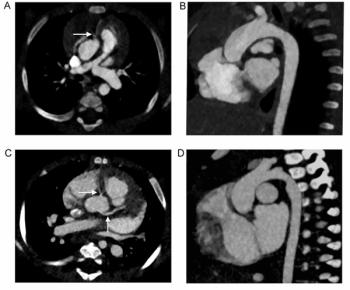

The updated Heartflow Plaque Analysis software reportedly offers enhanced 3D visualization of plaque type, volume and distribution based on coronary computed tomography angiography (CCTA) imaging.

Use of the AI-powered Salix Coronary Plaque module, which offers detection of high-risk plaque within 10 minutes based off of CCTA scans, will reportedly qualify for $950 in Category 1 CPT reimbursement in 2026.

For patients who had coronary CTA for acute chest pain, emerging research found no significant association between plaque burden grades with CAD-RADS 2.0 and cardiac events.

In a new study comparing standard resolution and ultra-high resolution modes for patients undergoing coronary CTA with photon-counting detector CT, researchers found that segment-level sensitivity and accuracy rates for diagnosing coronary artery stenosis were consistently > 89.6 percent.